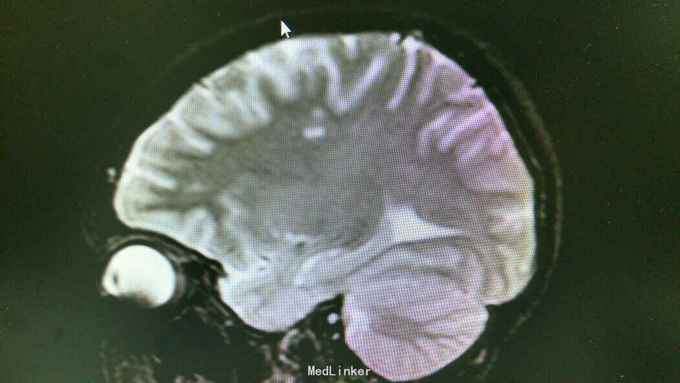

查体:T37.0℃,P110次/分,R26次/分,BP96/68mmHg。发育正常,营养一般,神志清楚,对答切题,轮椅送入院,查体合作。全身皮肤粘膜无黄染、皮疹,出血点及淤斑,未见Janeway结节,未见Osler结节及甲床下出血,无发绀,未见杵状指、趾,周围血管征阴性。浅表淋巴结未及肿大。巩膜无黄染,结膜无出血。口腔黏膜光滑,咽不红,扁桃体部大,颈静脉无明显搏动,未见怒张,气管居中,胸背部听诊双下肺闻及细小湿啰音。心前区无隆起或抬举性搏动,心尖搏动以左侧第六肋间锁骨中线外1.5cm处明显,未扪及震颤,心界向两侧稍扩大,心率110次/分,律齐,心音有力,P2稍亢进,无固定分裂,心尖区闻及3-4/6级收缩期吹风样杂音,向心底部传导,未闻及舒张期杂音,未闻及心包摩擦音。腹平软,无压痛及反跳痛,肝脾肋下未及,肠鸣音正常。脊柱、四肢关节无异常,活动好,双下肢无浮肿。 2015年10月30日汕头市中心医院心彩超:二尖瓣及瓣下腱索及左室心内膜多发赘生物形成,二尖瓣前瓣穿孔,重度二尖瓣关闭不全,左心系统扩大,心肌舒张功能下降,收缩功能正常,感染性细菌性心内膜炎,微量心包积液。 2015-11-1血常规:中性粒细胞比例 0.949,血红蛋白浓度 117.000(g/L),中性粒细胞计数 18.360(10E9/L),白细胞计数 19.350(10E9/L),血小板计数 343.000(10E9/L),红细胞计数 4.350(10E12/L)。 B超:双侧颈动脉血流通畅,双侧椎动脉未见狭窄。双侧甲状腺不大、未见占位,血供尚丰富。双侧颈部淋巴结声像,双侧乳腺未见明显占位,超声BI-RADS分类1类,双侧腋窝淋巴结声像。双肾未见结石与积水,双肾动脉主干血流连续,膀胱未见明显结石,双侧肾上腺区未见明显占位。肝脾胰不大,未见占位,胆囊未见明显结石,子宫及双侧附件区未见明显占位,宫后积液(少量)。 胸部CT:1、两下肺叶后基底段局部节段性肺炎。右肺中叶少许纤维化病灶。2、双侧胸腔少量积液。 胸片:考虑双肺炎症。 心电图:心率84次/分,窦性心律,肢体导联低电压,前间壁R波上升不良。 心彩超:1、考虑感染性心内膜炎:二尖瓣赘生物形成,伴中重度二尖瓣反流。中度三尖瓣反流。3、左房内径增大,肺动脉增宽。 头颅MR:左侧额叶、左侧放射冠侧脑室前角旁脑白质异常信号,考虑感染性病变及缺血灶可能性大。 2015-11-2查血常规:中性粒细胞比例 0.840,血红蛋白浓度 103.000(g/L),中性粒细胞计数 14.730(10E9/L),白细胞计数 17.540(10E9/L),红细胞计数 3.890(10E12/L),血小板计数 353.000(10E9/L)。 10月31日左上肢、右上肢、下肢血培养均提示:草绿色链球菌,对万古霉素敏感。 2015-11-6肾功能:肌酐 130.000(umol/L),尿素氮 5.250(mmol/L),二氧化碳结合力 30.500(mmol/L),电解质:钠 138.000(mmol/L),氯 96.000(mmol/L),钾 3.500(mmol/L),钙 2.310(mmol/L),肝功能:白、球蛋白比例 1.300,未结合胆红素 10.500(umol/L),总胆红素 17.900(umol/L),丙氨酸氨基转移酶 31.000(U/L),总蛋白 75.000(g/L),球蛋白 32.000(g/L),白蛋白 43.000(g/L),结合胆红素 7.400(umol/L),门冬氨酸氨基转移酶 31.000(U/L),脑钠肽:191.400(pg/ml)。 24小时心电图:窦性心律,房性早搏,部分成对,短阵房速,多源室早,部分成对,部分呈三联律,短阵室速。

关于感染性心内膜炎此前我发布过一个病例,但不同的病例有不同的特点和经验教训。上次的病例病变范围大,累及多瓣膜,治疗的难度在手术关,因手术过程复杂、手术时间长、对患者全身打击影响大,但上一个病例术前感染控制良好,在全身情况明显好转的情况下手术。此次发布的这个病例赘生物累及的瓣膜无上例多,但本例患者术前感染无法控制,反复高热、寒战,且赘生物大且形态呈“甩鞭样”,随时可能脱落栓塞周围脏器,另头颅MR报告左侧额叶、左侧放射冠侧脑室前角旁脑白质异常信号,考虑已有部分小栓子脱落栓塞脑血管形成小的感染性病变及缺血灶可能性大。因此综合考虑上述因素决定无法等患者全身状态好转在所谓的“理想状态”下手术,必须冒风险尽快行手术治疗,否则患者全身情况会进一步恶化并且可能发生脑栓塞,因此失去手术时机并可能导致死亡。术中需仔细清除干净感染的赘生物,术后积极强心、利尿、支持治疗并且敏感抗生素治疗4周。该病例术后出现反复双侧胸腔积液及心包积液,上一个病例也曾出现胸腔积液,考虑与患者术前全身状况不佳、心功能差及感染性心内膜炎所致的全身败血症及感染微栓有关。